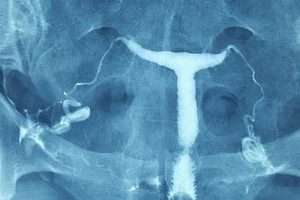

“T” Şeklinde Rahim

“T” Şeklinde Uterus